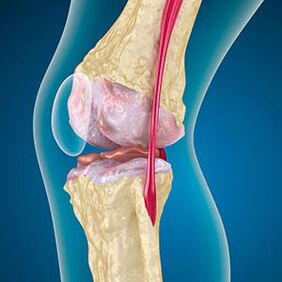

In the case of osteoarthritis, the cartilage that lines the edges of the bones is an abrasion or missing.Damaged tissue is not a source of pain because it has no receptors.Inflammation in nearby structures cause characteristic symptoms.

The body continues the regeneration of damaged tissues, but the cartilage grows unevenly.As a result, irregularities are formed that violate other elements of the joint.The type of osteophyte is declared smooth articular cartilage by compensation.Another version shows that the growth of "Spurs"It is associated with the attempt to stabilize the joint in the media or laterally due to the muscle weakening.

Arthrosis of the knee joint combines two processes: the destruction of cartilage and the growth of osteophytes or bone spores.The stage of the process is determined by the X -ray image.It is assumed that arthrosis is the destruction of the knee joints with the age, the natural process of aging.The causes are muscle weaknesses and poor blood supply to the tissue.How can you treat yourself without surgery?Remove factors that reduced the muscle tone.